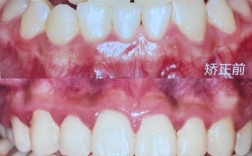

正畸模型测量是口腔正畸诊断与治疗设计中的核心环节,通过获取患者牙列、牙弓及咬合的精确数据,为制定个性化矫治方案提供客观依据,其测量内容涵盖牙冠形态、牙弓大小与形态、咬合关系、牙齿排列等多个维度,结合传统石膏模型与数字化扫描技术,实现对错牙合畸形的全面评估。

咬合关系是正畸评估的重点,直接影响咀嚼功能与面部美观,测量内容包括覆牙合、覆盖、中线偏斜及牙合曲线。

中线偏斜:测量上颌中切牙中缝与下颌中缝的水平距离,反映上下颌骨与牙列的对称性,中线偏斜可能由单侧后牙早接触、下颌偏斜或牙量骨量不调导致,需结合颞下颌关节检查明确病因。